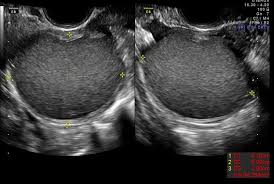

Có 180 bệnh nhân bị LNMTC giai đoạn 3 và 4 và mong muốn có thai, được điều trị từ tháng 6/2010 đến tháng 3/2015. Những bệnh nhân này đến khám vì vô sinh hoặc đau vùng chậu, bị LNMTC thâm nhiễm sâu hoặc có u LNMTC ở buồng trứng lớn hơn 3 cm. Những phụ nữ chỉ bị LNMTC nông hoặc ứ dịch vòi trứng thì không được nhận vào nghiên cứu. Quy trình phẫu thuật để cắt bỏ u LNMTC ở buồng trứng được thực hiện với năng lượng ion hoá (plasma energy) kèm theo cắt bỏ nhiều vị trí khác nhau của tổn thương. Sự thụ thai sau phẫu thuật được định nghĩa là thụ thai tự nhiên hoặc sử dụng các kỹ thuật hỗ trợ sinh sản.

Bệnh nhân được chia thành hai nhóm theo nồng độ AMH trước mổ: Nhóm A (AMH ³ 2 ng/ml) và Nhóm B (AMH < 2 ng/ml). Xét nghiệm AMH được thực hiện trong vòng 1 đến 12 tuần trước khi thực hiện phẫu thuật và 2 tháng sau phẫu thuật. Nồng độ AMH trước mổ lần lượt là 4,3 ± 2,1 ng/ml trong nhóm A và 1 ± 0,5 ng/ml trong nhóm B (p < 0.001). Sau phẫu thuật, nồng độ AMH lần lượt là 3,4 ± 2,5 ng/ml và 1,2 ± 0,9 ng/ml (p = 0.001).